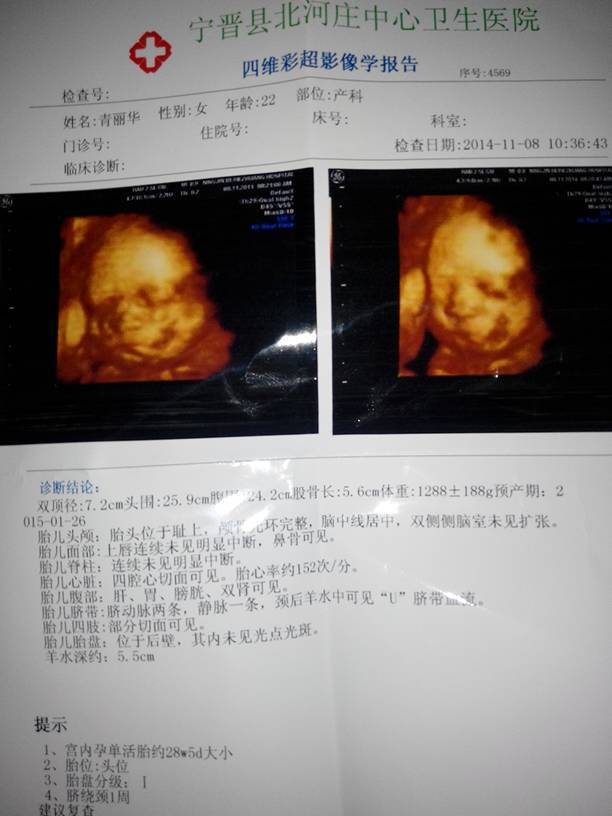

四维归来,懂的宝妈看看正常吗????? 四维归来,懂的宝妈看看正常吗????? 点击展开 永远有 多远 2014-11-11 14:34 为您推荐: 其他回答 你家宝宝好胖噢 ╭ァ幸福由╮我独家赞助 2014-11-11 16:39 单上不是有说明吗!上边都写正常就证明宝宝很健康啦! 天很蓝 2014-11-11 16:20 正常 的吧 宝贝锐锐 2014-11-11 15:18 哇塞我们的预产期只差两天 180*****303 2014-11-11 15:08 宝妈,你的四维彩超正常的 唯爱@永生 2014-11-11 14:39 加载更多 相关问题 宝妈,帮忙看下男女宝宝?谢谢!!四维归来! 有看得懂羊穿报告的宝妈么?给看看是正常的吗? 宝妈们我看看我做的四维有什么为题吗